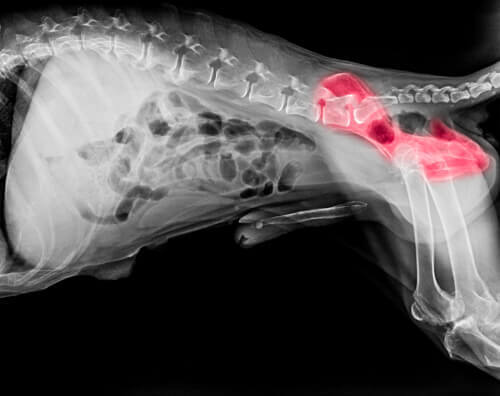

In relazione alle capacità motorie, i pastori tedeschi sono inclini alla zoppia ciclica. Di solito è più frequente nei maschi, ed è caratterizzata da una zoppia piuttosto “capricciosa”: può comparire e scomparire in uno qualsiasi degli arti, anche se di solito scompare con la crescita del cane.